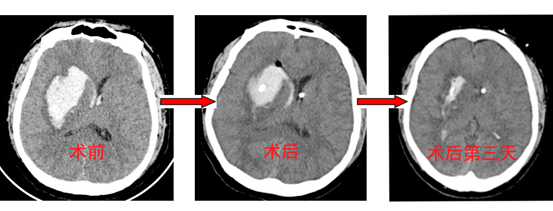

患者李先生突发脑出血陷入昏迷,CT影像上,血肿像定时炸弹般压迫着生命中枢。令人惊叹的是,神经外科团队启用的手术机器人,仅用2小时就完成传统需要开颅6小时的高危手术,在发丝粗细的误差范围内打通“生命通道”。标志着泰达医院在神经外科智能医疗领域取得突破性进展。

43岁的李先生突发意识障碍伴左侧肢体瘫痪3小时紧急入院,CT检查显示右侧基底节区出血量达50ml,血肿已破入脑室,病情危重。经评估,神经外科团队果断启用最新“黑科技”:神经外科手术机器人系统,行脑血肿穿刺抽吸技术。

主治医师汤其华利用机器人的引导,精准定位穿刺小骨孔,完成对血肿的抽吸,仅用2小时便完成手术,不仅快速解除血肿压迫,又避免传统穿刺的定位偏差问题。

术中成功清除30ml血肿,成功的将引流管的头端,精确的放置于脑出血的中心,术后患者生命体征平稳,肌力有所恢复(左上肢肌力恢复至2级,左下肢肌力恢复至3级)。